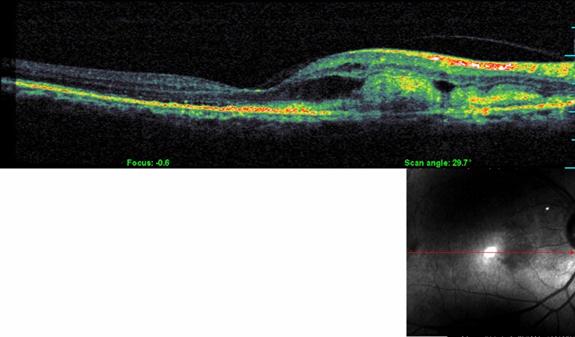

Optical Coherence Tomography (OCT)

OCT is a non-radiation mode of scanning that utilizes certain light waves for the scan.

OCT can show the retinal layers almost as if in biopsy (layer by layer). The resolution of the Spectral OCT scan available in MEH is 5 microns. Such highly precise scans help your doctor diagnose your AMD quite effortlessly.

• leading eye hospital for AMD treatment

Normal OCT

• top eye hospital for AMD

OCT in AMD

• best eye hospital for macular degeneration in Kerala

OCT is the most sensitive scan for monitoring the progress of AMD as well as for assessing the response to treatment.